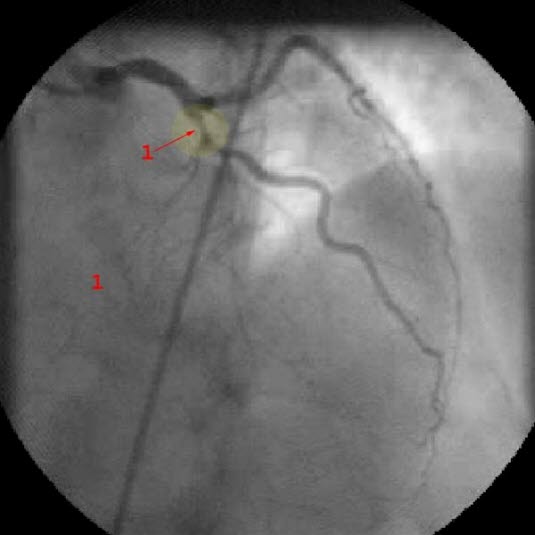

Diagnosen bygger i all hovedsak på sykehistorien. Det vil si de symptomer og tegn som du selv merker. Ved raskt økende brystsmerter av den beskrevne typen bør du ta kontakt med lege snart. Som regel vil det være aktuelt å legge deg inn på sykehus til observasjon og behandling. EKG og blodprøver vil avklare om det er angina eller om det er oppstått et akutt hjerteinfarkt. I de fleste tilfeller vil det være aktuelt å ta bilder av koronararteriene dine i forbindelse med hjertekateterisering (se video nedenfor).

Tidlig etter innkomsten vil legene vurdere om du bør få utført utblokking av koronararterien(e) som er blitt trange - inngrepet kalles perkutan koronar intervensjon (PCI). Andre betegnelser er hjertekateterisering eller koronar angioplastikk. Jo høyere legene vurderer din risiko for alvorlig sykdom og forløp, jo riktigere er det å gjøre PCI. Helst vil man gjøre det innen 12-24 timer.

Ved PCI føres et kateter inn i den trange blodåren, åren vides ut og i de fleste tilfeller setter man inn en stent. Stent er en type armering som skal forebygge at blodåren raskt lukker seg igjen. Andre ganger kan det bli nødvendig med en åpen hjerteoperasjon der man syr inn en ny blodåre forbi den eller de årene som er trange (bypass-operasjon).